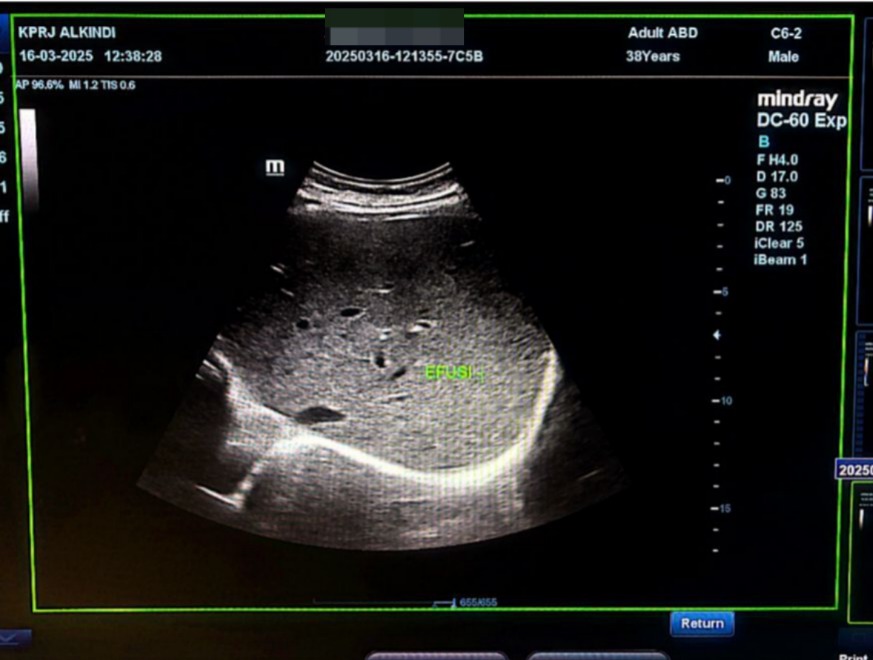

Pada pemeriksaan USG Abdomen ( 16-02-2025) didapati akumulasi cairan pada kantung paru(efusi pleura) , kantung perut( Ascites)

Pada pemeriksaan USG Abdomen 16-03-2025 tidak didapati akumulasi cairan pada kantung paru( efusi) dan juga kantung perut (ascites)